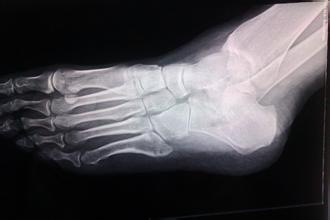

核心提示:骨折是指骨结构的连续性完全或部分断裂。多见于儿童及老年人,中青年人也时有发生。病人常为—个部位骨折,少数为多发性骨折。经及时恰当处理,多数病人能恢复原来的功能,少数病人可遗留有不同程度的后遗症。想了解...